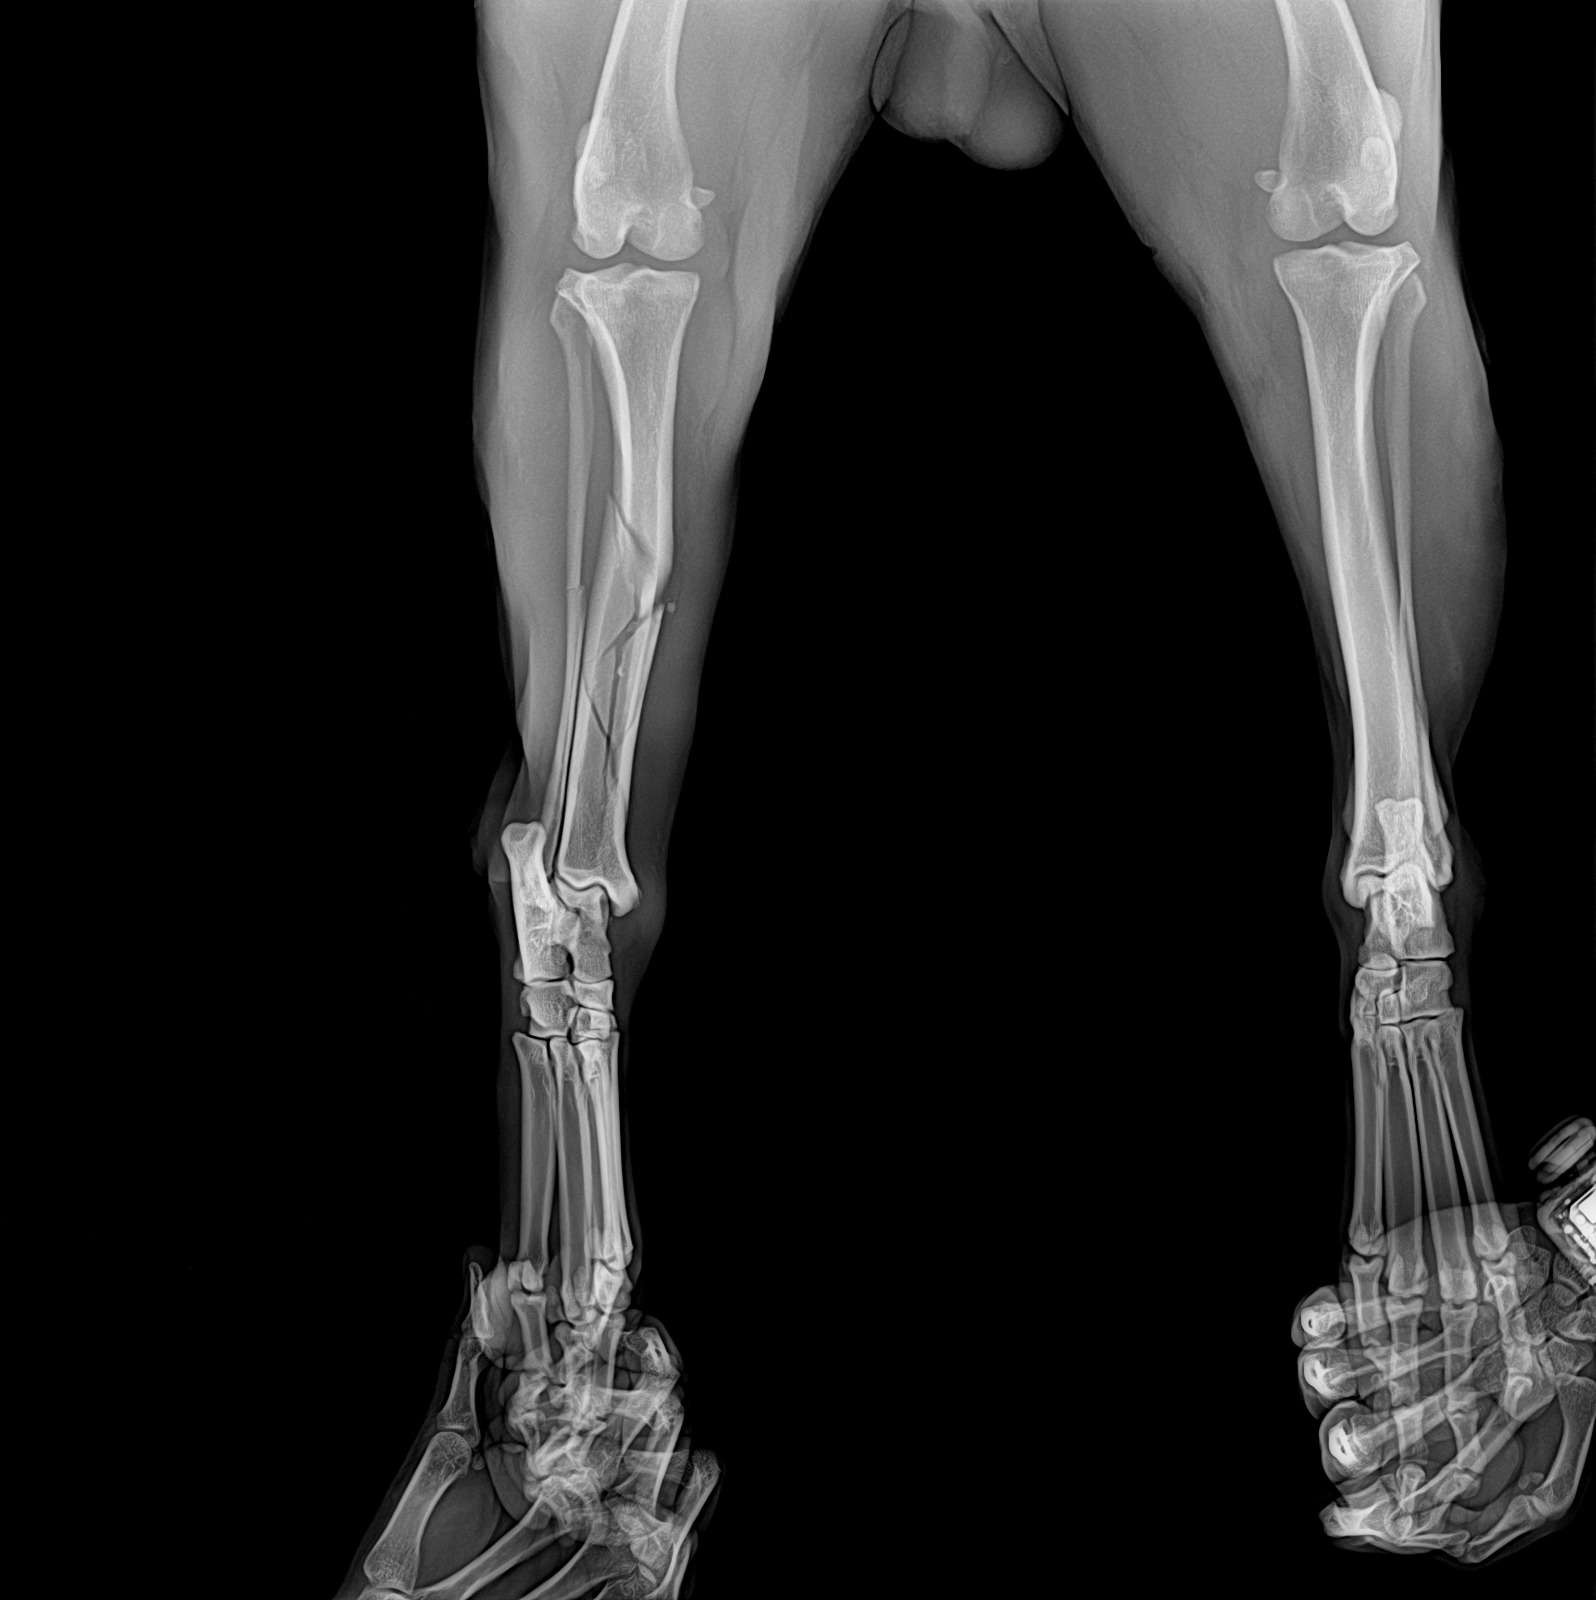

Hello Everyone, this sweet boy is Ace (his rescue name) he was found on December 25 injured and with a broken leg, he entered a local store to try to seek shelter after he was likely hit by a car and got into a fight with another dog, he has multiple bite wounds all over his body and his tibia is shattered.

Once we got the results of the x-rays and his check up we realized the we likely would not be able to cover the bill on our own, but we don't want to leave Ace to his own luck so we've decided to start this gofundme to try and get the money for his surgery and subsequent recovery as he will need a lot of care and love before he is ready to look for a forever home that will love and care for him for the rest of his life.